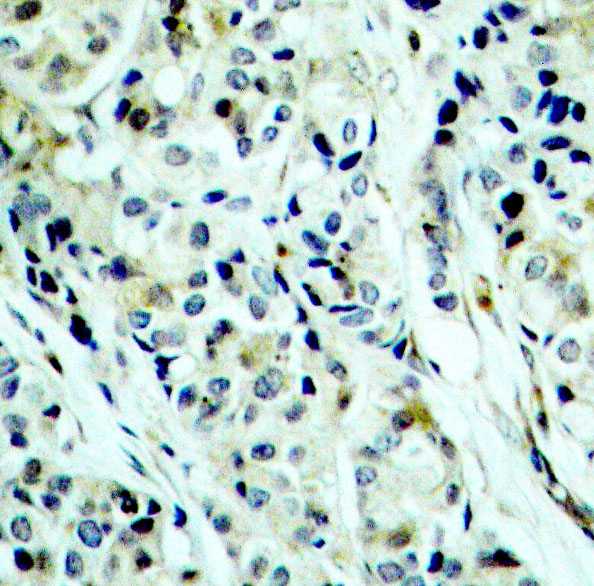

Immunohistochemistry of paraffin-embedded human breast carcinoma using Phospho-HDAC5-S498 antibody. |